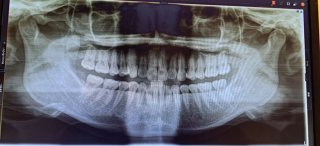

45歳女、5年越しにワイヤー矯正を決断! 2023.4.20(木)

新型コロナが流行する前、医師から「健康的な自前の歯」を維持するべく、ひとつの選択肢として歯科矯正を勧められたアラフォー...